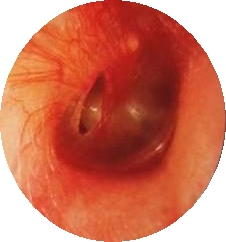

외상에 의한 고막 천공은 소리의 전달에 중요한 역할을 하는 고막이 외부의 충격에 의해 찢어지거나 구멍이 나서 손상되는 것을 말합니다.

귀의 통증은 오래가지 않지만 고막이 온전하지 않으므로 청력이 감소하고 귀울림이 있을 수 있습니다. 고막이 손상을 입으면서 고막 주변에 출혈이 발생하여 귀 밖으로 피가 흘러나오기도 합니다. 만약 귀 밖으로 고름이 나오면 손상된 고막 주위에 이차적인 세균 감염이 발생했을 가능성이 있습니다. 고막뿐만 아니라 귀안의 다른 구조물에도 손상이 생겼다면 청력이 크게 감소하거나 어지럼증이 발생할 수도 있습니다.

고막의 손상 여부는 이경이나 귀 내시경을 이용해 고막을 진찰하여 진단할 수 있습니다. 고막을 진찰하여 고막이 파열된 부분의 위치와 크기 등을 확인합니다. 고막 파열로 인한 청력 감소의 정도는 청력 검사를 통해 확인할 수 있습니다. 고막뿐만 아니라 귀안의 다른 구조물의 손상이 의심되는 상황이라면, 측두골 단순 방사선 검사나 CT 검사를 받을 수도 있습니다.